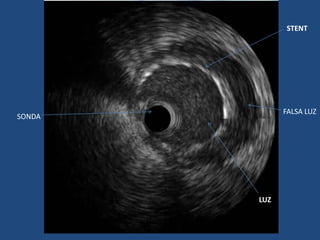

STENT

FALSA LUZ

SONDA

LUZ

IVUS features indicating that the intramural hematoma derives from a spontaneous coronary

dissection.

Porto I et al. Circ Cardiovasc Interv 2010;3:519-522

• IVUS asegura que la guía esté en la verdadera luz y que tras el

implante del stent no se haya producido una propagación de

la disección o protrusión de trombo por uno de los extremos.